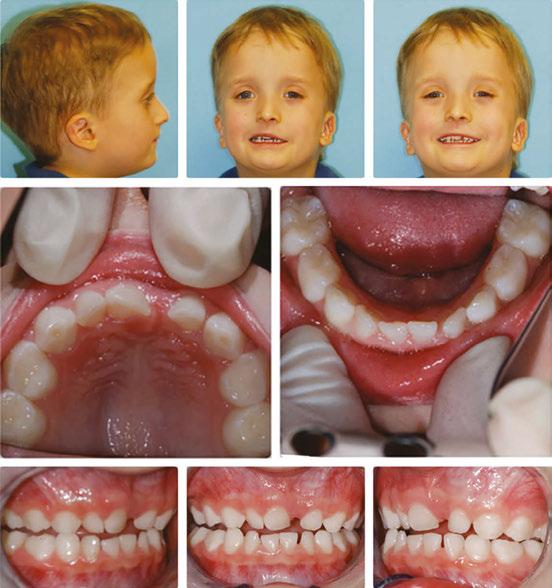

Over 10 years ago, we began Orthotropic® treatment for a 5 year, 3-month-old boy with a diagnosis of Pierre-Robin Sequence, Obstructive Sleep Apnea (OSA), and Failure to Thrive (Figure 1). With lack of forward development of the face com-

monly seen in Pierre-Robin patients, his airway was compromised, resulting in OSA. The Failure to Thrive diagnosis likely resulted from insufficient growth hormone being released during the deeper stages of sleep. This treatment began before any permanent teeth erupted. Our goal was to eliminate OSA.

Orthotropics® uses removable appliances to laterally expand the upper arch while simultaneously advancing the upper anterior teeth to their proper place in the face. Then the mandible is developed forward. Orthotropics® is my preferred treatment in cases like this because it negates the head gear-effect producing better facial balance5 and also can result in substantial airway improvements (Figure 2).6

This young boy had great parental support and was very compliant during the treatment. A posttreatment sleep test showed no signs of sleep apnea.7 Failure to Thrive was also overcome. Now at 17 years old, this patient is 5 ft. 7in. tall and is still growing. I believe that improved breathing and sleep has resulted in an increase in HGH production which allowed him to resume normal growth. He’s an aggressive tennis player with a big smile and no return of his OSA (Figure 3). Thankfully, he’s an excellent student with no evidence of brain damage from his early OSA diagnosis.

Figure 1: Pretreatment gallery Figure 3: Today, he’s a tennis player Figure 2: Pre- and posttreatment airways